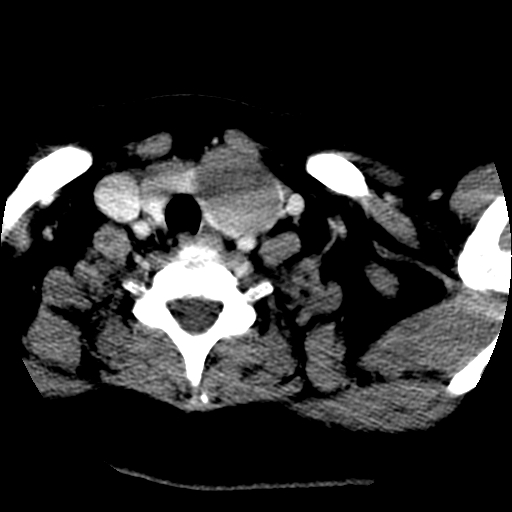

考虑右叶结节性甲状腺肿,伴左叶钙化。主要(1)密度均匀,边境清。(2)病灶与血管界限清。

考虑左侧甲状腺结节性甲状腺肿,不排除甲状腺腺瘤。

考虑左侧甲状腺腺瘤囊变。